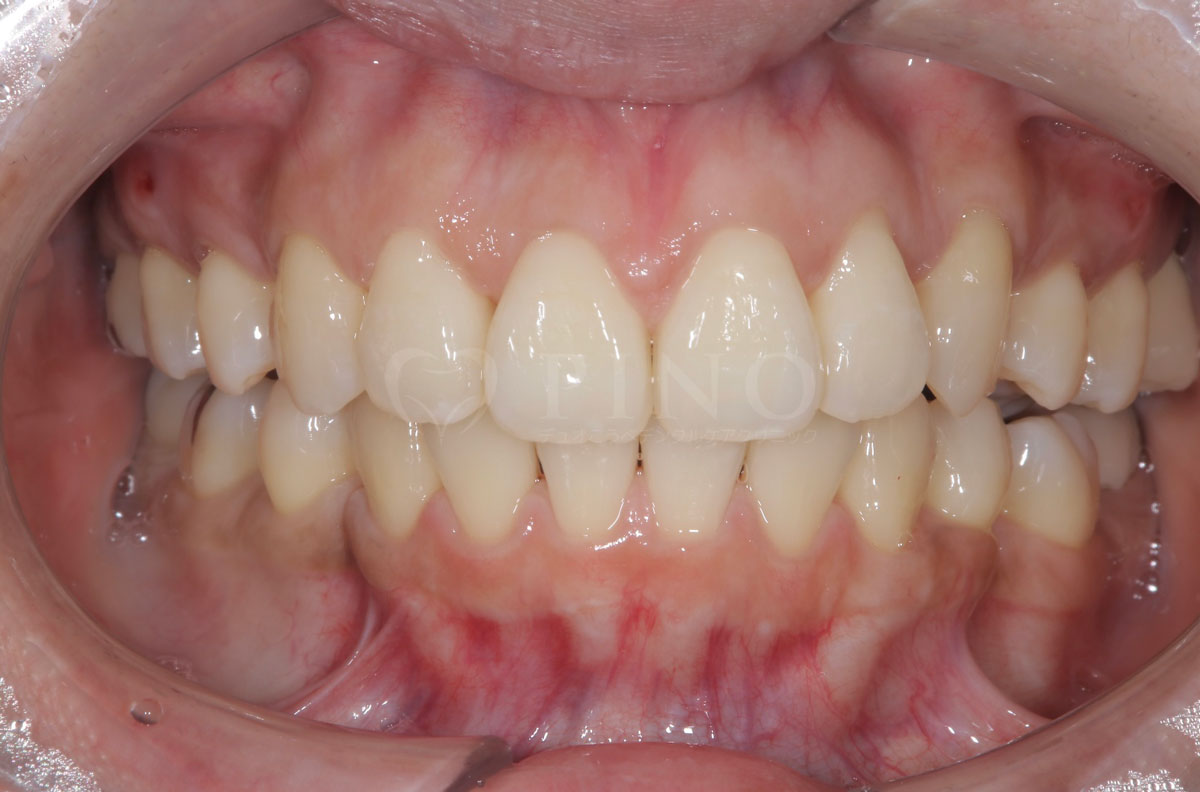

症例8:歯が全体的にガタガタして気になる(30代女性)

主訴 歯が全体的にガタガタして気になる 診断名 上下顎1級叢生 治療方法 マウスピース全顎矯正 抜歯 あり 上2本 オルソパルス あり 治療期間 1年5ヶ月 費用 891,000円+補綴治療費(セラミック320,000円) 副作用・注意点 歯を抜く際に痛みを伴う可能性がある、矯正後後戻りを防ぐためリテーナーの使用が必要となる -